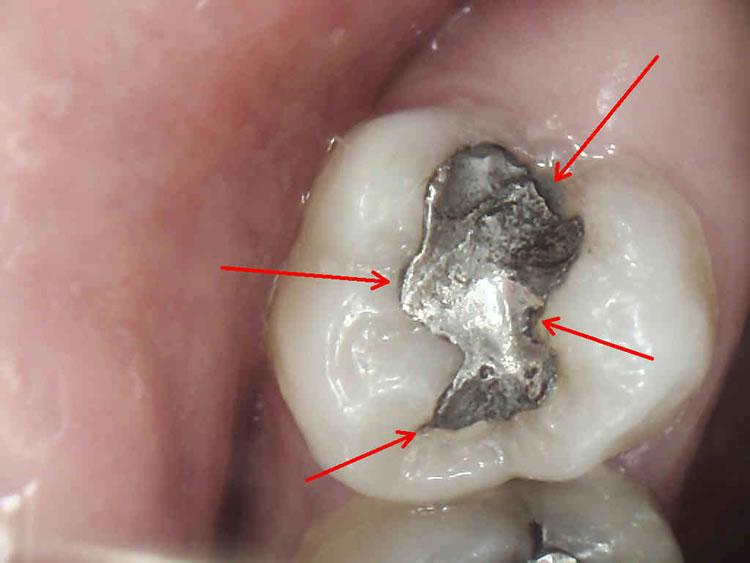

Svima dobro poznati, sivi, amalgamski ispuni, danas se iz zdravstvenih i estetskih razloga zamjenjuju estetskim, kompozitnim ispunima.

Naša su iskustva u praksi da redovno, ispod amalgamskog ispuna, u toku sanacije zuba pronalazimo karijes. Obrazloženje je u činjenici da se amalgam kao materijal za ispun s vremenom skvrčava i time stvara pukotinu između sebe i stjenke zuba. To naravno dovodi do prodora bakterija karijesa u kavitet na zubu a time i kvarenja zuba.

Estetski ( bijeli ) materijali ne mijenjaju volumen tijekom vremena. Dakle, nema pukotine, nema prodora bakterija i nema kvarenja zuba.

Postavljanjem estetskog materijala postižemo kvalitetnu rekonstrukciju zubnog tkiva i potpuno prirodan izgled za razliku od ( sivog, metalnog ) amalgamskog ispuna.

Za izradu estetskog ispuna potrebno je odstraniti samo bolestan dio zuba za razliku od amalgamskog ispuna za koji je bilo potrebno odstraniti i dio zdravog zubnog tkiva zbog držanja amalgama u zubu.